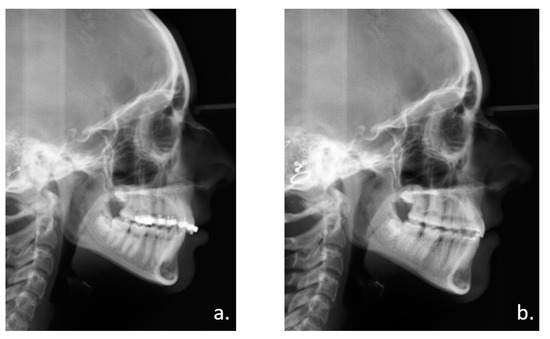

Like any distraction treatment, IMDO is a dynamic procedure that requires regular radiological and clinical monitoring (Figure 3, Figure 4 and Figure 5).

Figure 5.

Clinical follow-up. Photographic documentation of two patients: (a) 12-year old patient with class II/2 occlusion before and after end of combined orthodontic and IMDO treatment. (b) 12-year old patient with class II/1 occlusion and traumatic deep bite before and after end of combined orthodontic and IMDO treatment.

Detailed case data descriptions are provided in Table 1. In total, 20 patients (11 male and 9 female) with a mean age of 14.8 (SD = 0.9) years were included. In all cases, the combined orthodontic-surgical treatment was successfully completed. Patients had little facial swelling postoperatively and pain medication was needed for only one week in most patients. An average gain in horizontal mandibular length of 9.6 mm (SD = 3.7 mm) could be achieved. In one patient, premature bone maturation was seen in the distraction gap, forcing re-osteotomy.

All patients achieved a Class I occlusion, which remained stable until the data collection of this publication. Infections that would have led to premature distractor removal were not observed. However, in one patient an abscess in the region of the activation rod had to be treated by evacuation. No functional impairment of the sensitive function of the third branch of the trigeminal nerve was noted. In nine patients, fractures of the mesial root of the second molar occurred at different levels during osteotomy (Figure 6). Three second molars had to be removed, one molar with root fracture was treated endodontically. Resorptions of the fractured root fragments were seen during follow-up.